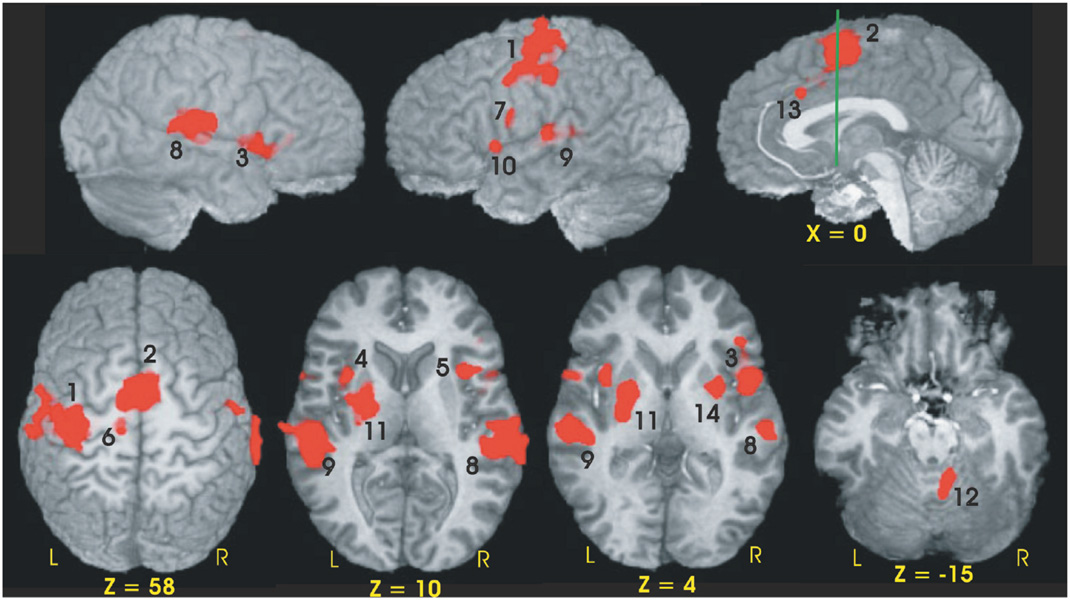

fMRI Activation Results

Fourteen functional ROIs were identified from the conjunction analysis performed across the three groups (see Table 3, Fig. 2). Using percent MR signal change as the dependent measure, a 2 (condition) × 3 (group) ANOVA was performed for each fROI. Four of the 14 fROIs demonstrated main effects of condition (S vs. C). As expected from our previous fMRI study of young healthy participants (Rao et al., 1997), fROIs exhibiting greater neural activation during the C condition relative to the S condition included the left sensorimotor cortex (SMC, p = .001) and medial premotor cortex (bilateral SMA/preSMA/CMA, p < .001). Greater activation during the S relative to the C condition was observed in the left and right superior temporal gyri [STG] (p < .001); this was expected since no auditory stimulus was presented during the C condition.

Functional ROIs and volumes of the conjunction mask

Functional ROIs of the conjunction map used to evaluate group differences in MR signal intensity. Numbers adjacent to activation foci correspond to numbers in brackets in Table 3. The green line in the sagittal image (x = 0) is perpendicular to the AC-PC line and is positioned at the anterior commissure (y = 0).

Twelve of the 14 fROIs demonstrated main effects of group. Post hoc analyses revealed 3 distinct patterns of group differences. The first pattern revealed that the CLOSE group had significantly less activation relative to the FAR and CONT groups. This effect was observed in the left anterior insula, right inferior frontal gyrus, bilateral medial premotor area (SMA/preSMA/CMA), and left putamen (see Fig. 3). The second pattern, observed in the right anterior cingulate and right anterior insula, was characterized by a significant stepwise reduction in activation across the three groups (CONT > FAR > CLOSE; see Fig. 4). For the third pattern, the FAR group exhibited significantly increased activation relative to the CLOSE and CONT groups. This effect was observed in the left SMC, left precentral gyrus, left medial frontal gyrus, bilateral STG, and the right cerebellum (see Fig. 5). No significant condition by group interaction effects were observed in any of the 14 fROIs.

Percent MR signal change for each ROI in which the CLOSE group showed significantly lower activation relative to the FAR and Control (CONT) groups (i.e., CONT = FAR > CLOSE). Bracketed numbers refer to brain regions displayed in Fig. 2; error bars = SEM.

Percent MR signal change for each ROI in which a stepwise reduction in activation was observed between the three groups (i.e., CONT > FAR > CLOSE). Bracketed numbers refer t brain regions displayed in Fig. 2; error bars = SEM.

Percent MR signal change for each ROI in which the FAR group showed significantly greater activation relative to the CLOSE and Control groups (i.e., FAR > CONT = CLOSE). Bracketed numbers refer to brain regions displayed in Fig. 2; error bars = SEM.